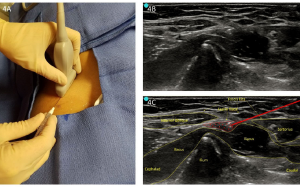

Figure 4. A: Infrainguinal approach (perpendicular to inguinal ligament). B: Unlabeled infrainguinal preprocedure scan. C: Labeled image with infiltration.